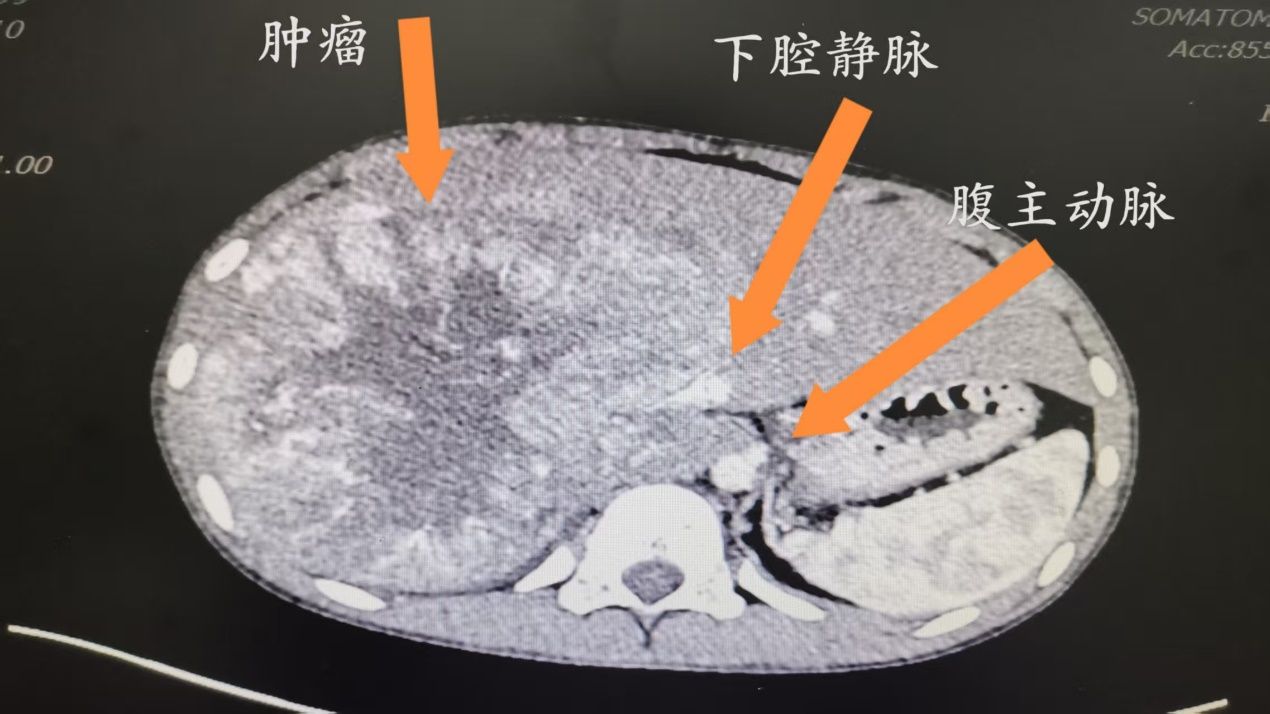

据李鹏教授介绍,该患儿2年前曾于宁夏某医院手术治疗后恢复良好。3月初复查时发现肝脏肿瘤,慕名来到我院,进一步完善各项检查,根据患儿病情和病理结果最终确诊肾上腺皮质癌伴肝转移,目前患儿一般情况良好,没有表现不适症状。该病在儿童中发病率仅为0.2~0.3/百万,属极罕见恶性肿瘤。影像显示,腹膜后肿瘤最大径约15cm,肝右叶存在转移并累及右半肝脏的血管、胆道,更为棘手的是肿瘤紧密包绕肝后段下腔静脉,导致影像学上的下腔静脉结构模糊。此类病例手术风险极高:既要尽可能彻底切除肿瘤,又需保护重要血管功能,稍有不慎可能导致大出血或器官损伤,对外科团队的技术与应变能力提出极致挑战。

5小时鏖战:精准“拆弹”零误差